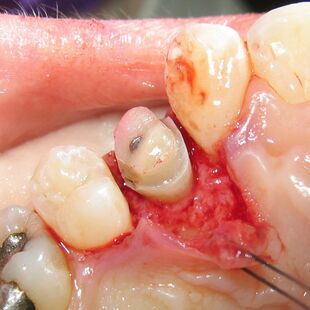

A palatal view of a maxillary premolar during a crown lengthening procedure. |